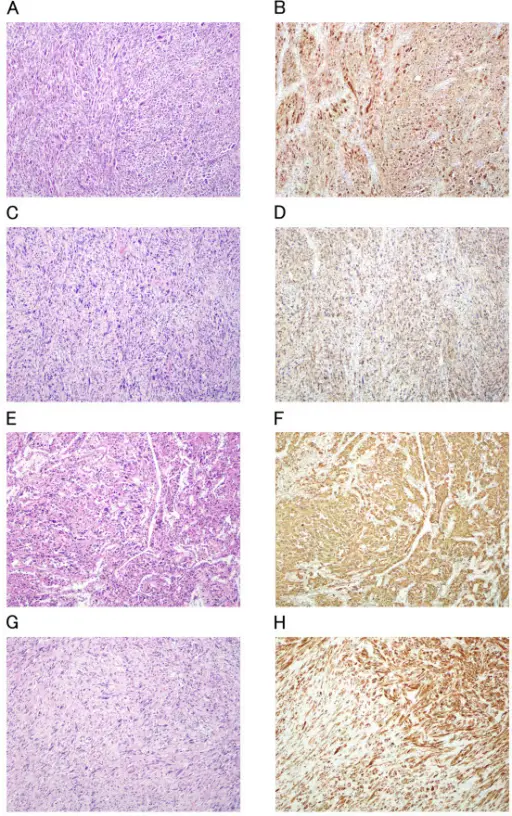

Myxomas are benign mesenchymal tumors.

Myxomas typically have a histologic appearance showing an abundance of ground substance and a gelatinous appearance.

Rhabdomyomas are benign hamartomas of cardiac muscle.

Patients with tuberous sclerosis are at increased risk of rhabdomyomas.